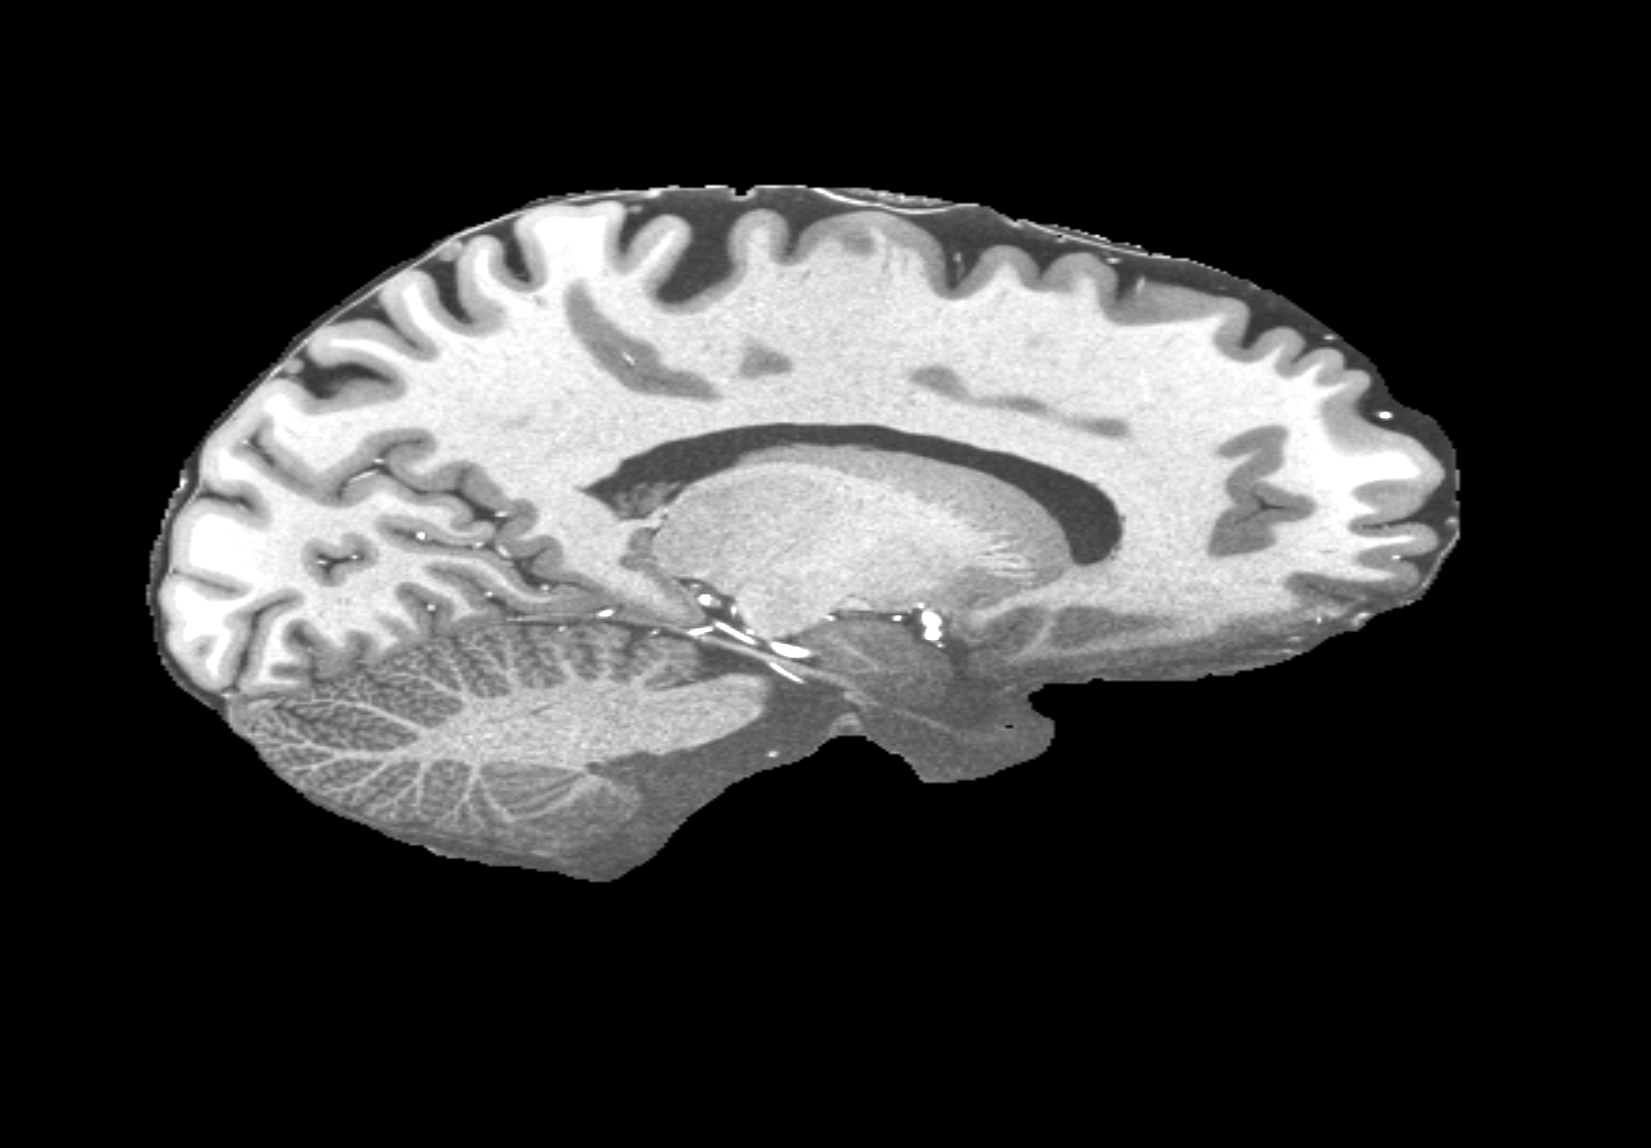

4.2 Registration to a 100 micron ex-vivo brain MRI volume

To showcase the efficacy of our method on real large scale images, we register a 250 in-vivo MRI image (Lüsebrink et al., 2017) to a 100 ex-vivo FLASH human brain volume (Edlow et al., 2019). This represents an inverse problem with more than 11.2B optimizable parameters (compared to 20M for clinical datasets), or 44.8GB of GPU memory. The entire problem does not fit on most GPUs, necessitating distributed multimodal registration. We optimize a composite transform - affine followed by a diffeomorphic mapping; details can be found in Section E.1. Multimodal deformable registration took 58 seconds on 8 NVIDIA A6000 GPUs, which is unprecedented at this resolution. Fig. 6 shows qualitative results, highlighting the ability to register highly detailed structures such as cerebellar white matter; these structures are not visible at macroscopic scales. The resultant advantages of performing registration at this scale can allow researchers to characterize the neuroanatomy at microscopic resolutions and allow morphometric analysis of cortical layers and subcortical nuclei among other structures.